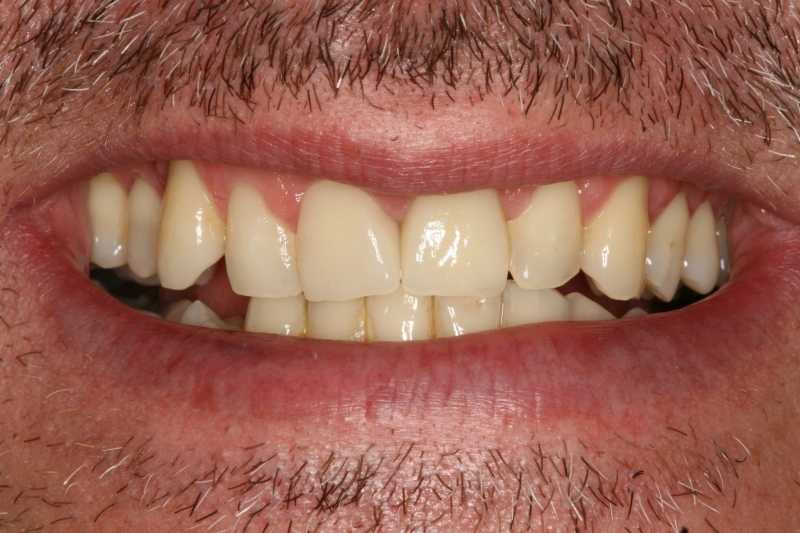

A végeredménnyel nem csak a páciensünk volt elégedett!

páciensünk elégedett a végeredménnyel